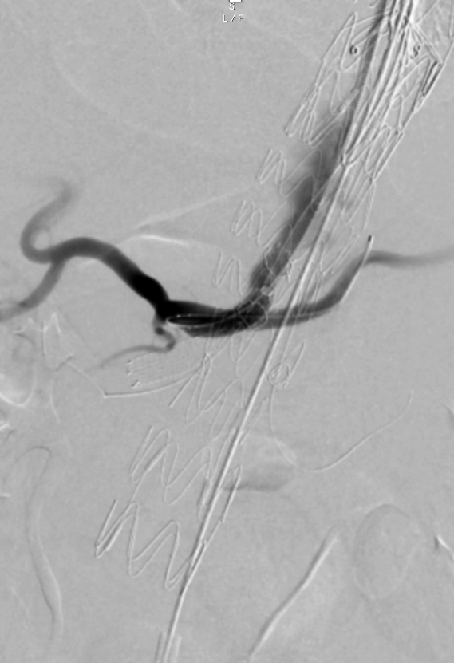

超选SMA,桥接8-100mm Viabahn,内衬8-60mm Absolute裸支架

超选CA,桥接8-100mm Viabahn

超选RRA烟囱支架,桥接6-100mm+6-50mm Viabahn

超选LRA烟囱支架,桥接6-100mm Viabahn

术后造影